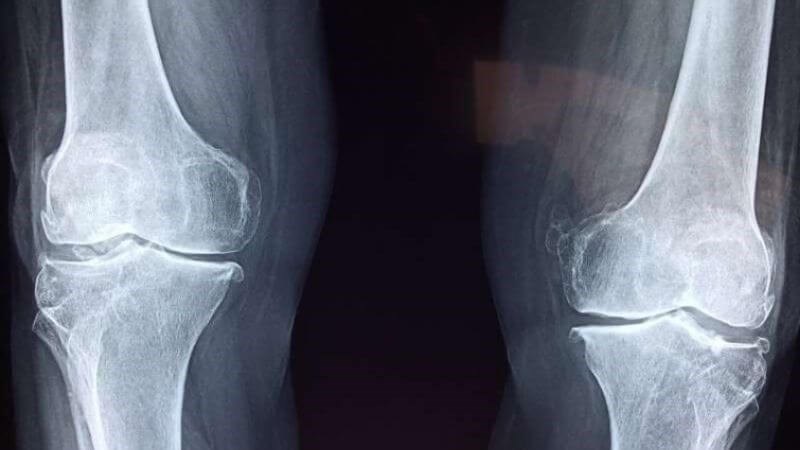

2Cây bìm bịp chữa xương khớp có tốt không?

Theo Y học cổ truyền, bìm bịp có vị ngọt, tính bình, quy kinh can đởm, có công dụng mát gan, lợi tiểu, giảm phù nề. Cây này thích hợp để chế biến các món ăn giải nhiệt, giúp làm mát cơ thể. Ngoài ra, bìm bịp còn hạ sốt, kháng viêm và giảm đau, chữa sưng đau, gãy xương, đau nhức xương khớp, bong gân và điều trị vết thương chảy máu.

Theo các nghiên cứu khoa học, bìm bịp chứa hàm lượng flavonoid cao có khả năng ức chế chu kỳ tế bào, hỗ trợ chữa viêm gan và bệnh ung thư. Cây còn chứa nhiều vitamin và khoáng chất như glycosid, tanin, cerebroside, glycerol giúp cầm máu, kháng viêm, giảm đau và hạ sốt. Do đó, bìm bịp rất hiệu quả trong việc hỗ trợ điều trị đau xương, gãy xương và bong gân.

Cây bìm bịp có khả năng hỗ trợ điều trị đau xương và gãy xương một cách tích cực